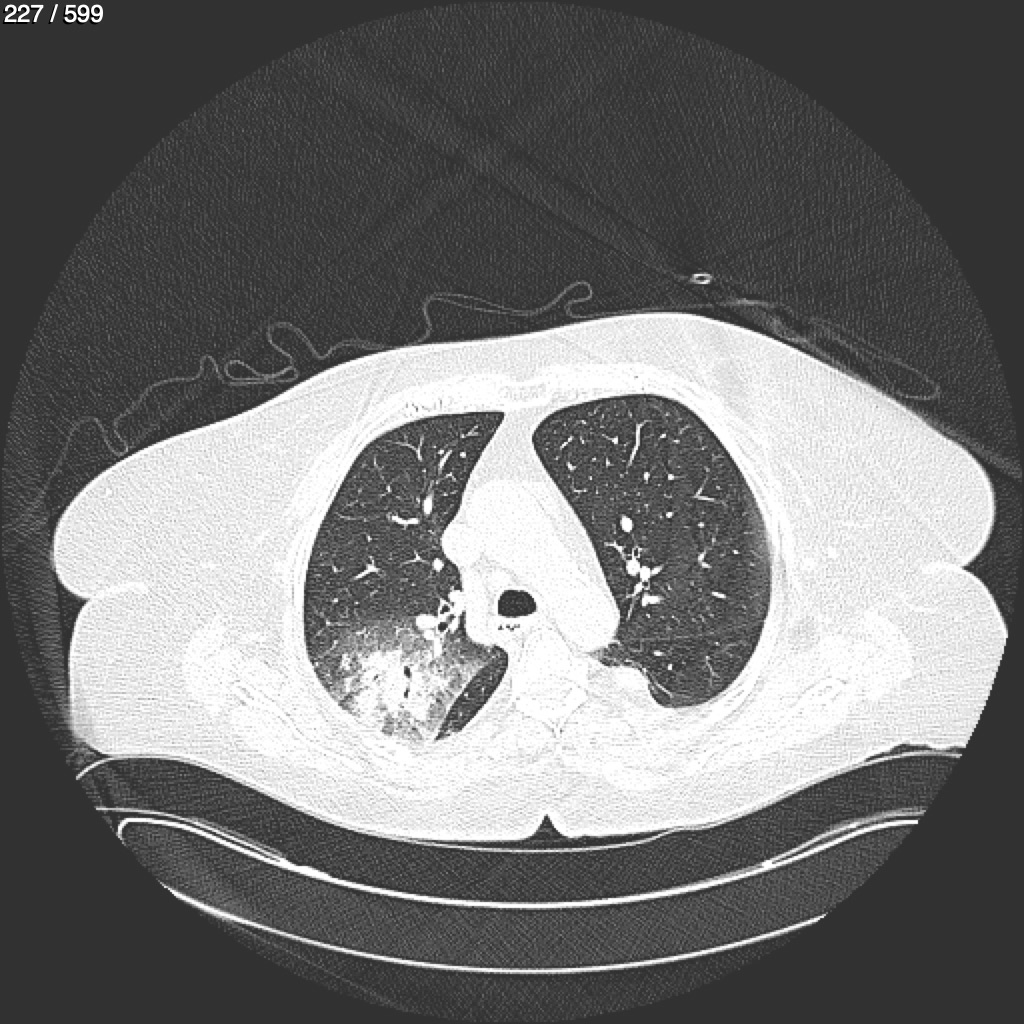

Home G​l​o​r​i​a​ ​G​l​a​d​y​s​ ​B​e​a​s​l​e​y​ ​-​ ​T​ó​r​a​x​ ​T​o​r​a​x​_​S​i​m​p​l​e​ ​(​A​d​u​l​t​o​)